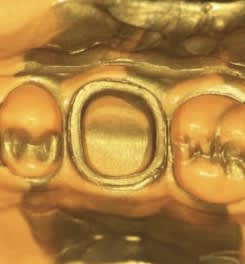

Pas de problème, allez je t’en prends une au hasard. Là je te mets une prothèse que je viens de poser. À coté tu vois une belle prothèse française faite par un ancien. Mon but n’est pas de critiquer l’ancien dentiste qui malheureusement a été obligé de poser ça parce que son prothésiste français ne pouvait pas mieux faire